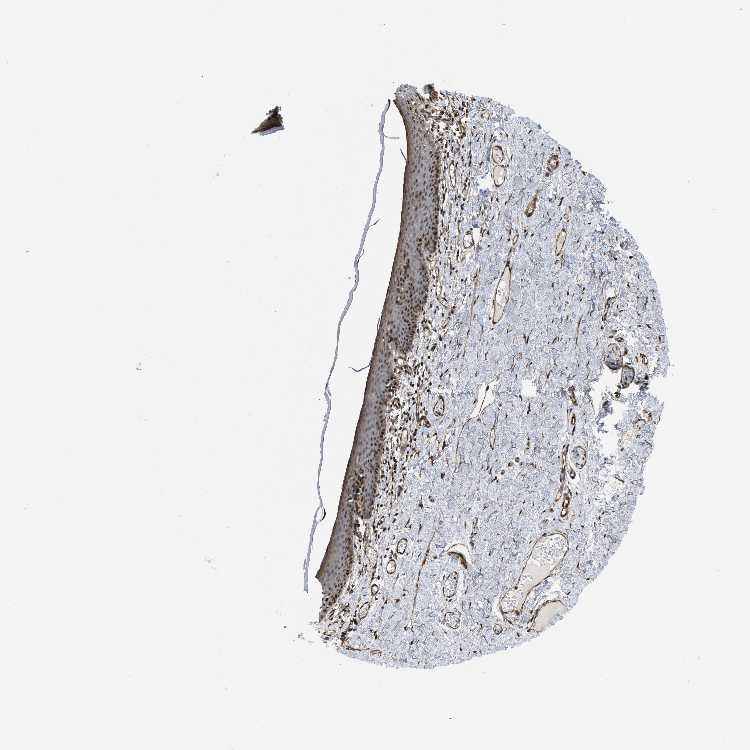

SKIN 2 - Antibody stainingi

Antibody staining in the annotated cell types in the current human tissue is reported as not detected, low, medium, or high, based on conventional immunohistochemistry profiling in selected tissues. This score is based on the combination of the staining intensity and fraction of stained cells.

Each image is clickable and will lead to virtual microscopy that enables deeper exploration of all samples and also displays staining intensity scores, fraction scores and subcellular localization as well as patient and tissue information for each sample.

Antibody HPA008399Antibody HPA017017Antibody CAB015221

Epidermal cells MediumMediumMedium